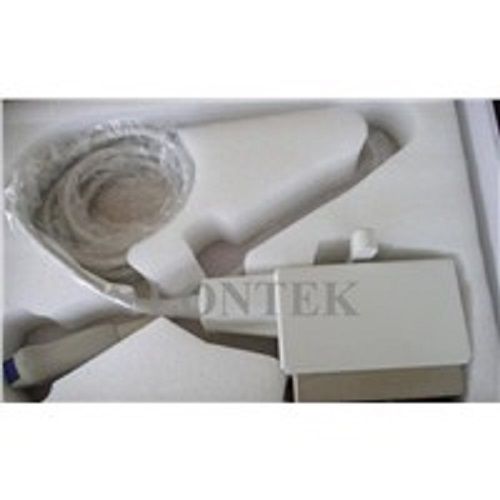

Samsung Medison Accuvix XG with 3D/4D convex probe

Sale price$ 47,965.06